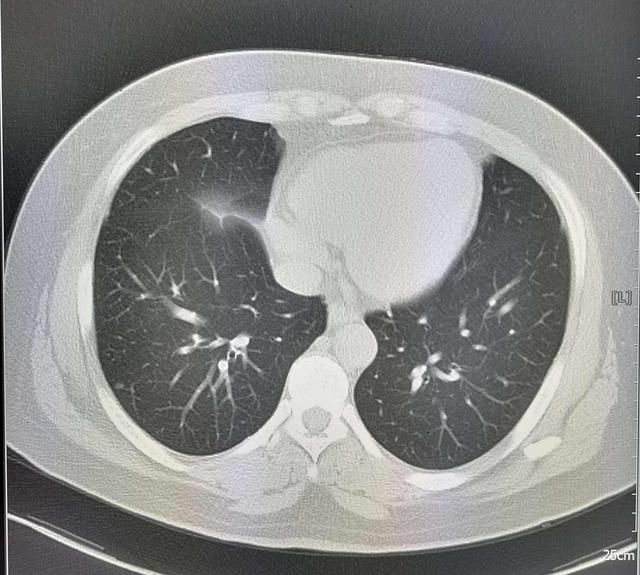

第三阶段的湿气 , 已经进入脏腑了 , 如果脾胃充满湿气 , 就会有胃胀胃疼的症状 , 如果肺里充满湿气 , 就会导致肺的宣泄功能失常 , 你会一直咳嗽不止;如果湿气进入了子宫 , 就很容易导致宫颈炎、盆腔炎了 。 这个阶段的治疗 , 需要根据具体情况进行辨证 , 如果肺的湿气重 , 可以用复方鲜竹沥液来调理;如果是脾胃有湿气 , 就可以用参苓白术散来调理 。

第四阶段的湿气 , 是最严重的一个阶段 , 湿气久聚 , 源源不断的化生成痰浊 , 而痰和湿又一直阻碍气血运行 , 形成血瘀 , 痰湿和血瘀包裹在一起 , 会生成囊肿、结节、息肉等包块 , 而且因为体内湿气重 , 包块会长得很快 , 也会越长越多 , 患者同时还会有失眠、胃炎、胸闷腹胀等问题 。 这个阶段的治疗 , 得健脾祛湿 , 化痰破瘀 , 可以用八珍汤加味丹参、三棱、香附等中药 。